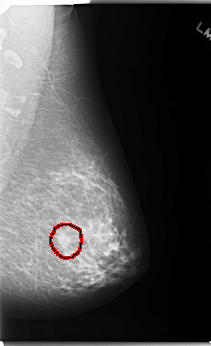

C_0124_1.LEFT_CC

FILE: C_0124_1.LEFT_CC.OVERLAY

TOTAL_ABNORMALITIES 1

ABNORMALITY 1

LESION_TYPE MASS SHAPE OVAL MARGINS SPICULATED

ASSESSMENT 5

SUBTLETY 5

PATHOLOGY MALIGNANT

TOTAL_OUTLINES 1

BOUNDARY